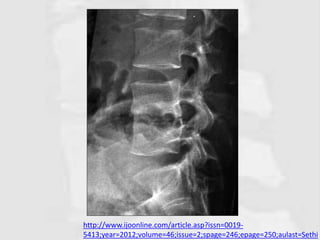

http://www.ijoonline.com/article.asp?issn=0019-

5413;year=2012;volume=46;issue=2;spage=246;epage=250;aulast=Sethi